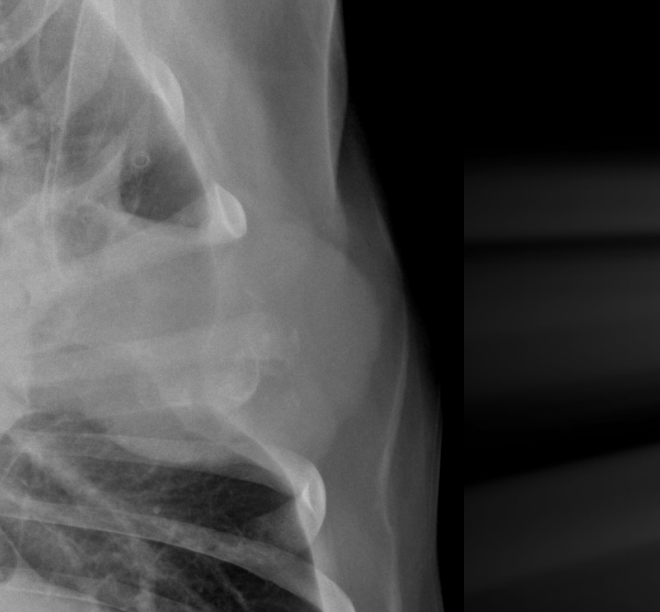

What is the chronicity of these rib fractures?

Left: acute

-displacement

-sharp margins

Right: chronic

-callus formation